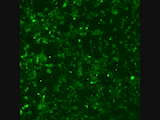

Die grünen Punkte sind Stammzell-derivierte Nervenzellen mit einem Kalzium-Farbstoff. Die Aktivität des Netzwerks zeigt, das die Nervenzellen nach 2 Wochen in Kultur „denken“, auch teilweise synchron.